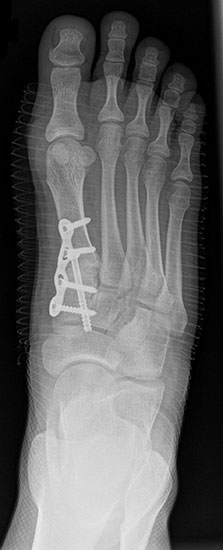

Röntgen

Standard ist die belastete Röntgenaufnahme des Fußes dorso-plantar und seitlich. Günstig ist eine Röhrenkippung von 10°-20°, um die Gelenke der Lisfranc-Linie einsehen zu können.

• medial aufklappende Cuneiforme I Osteotomie 1522

• Wachstumslenkung: Hemiepiphysiodese der lateralen Basisfuge am Metatarsale I  23

• Nach Schluss der Wachstumsfugen: TMT I Arthrodese nach Lapidus 2425